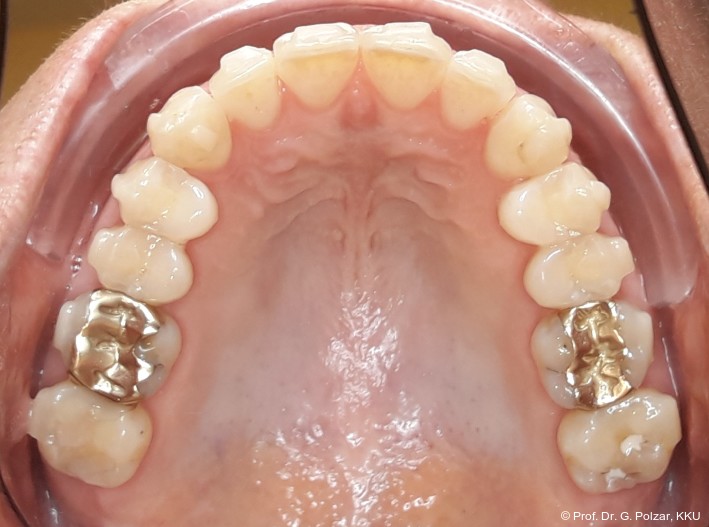

Der intraorale Befund zeigte eine scheinbar neutrale Verzahnung. Trotz Lingualretainer in der UK-Front war ein Engstand in der Unterkieferfront mit leichter Protrusion erkennbar. Appro­ximal des Zahnes 41 waren deutliche schwarze Dreiecke zu erkennen, zudem wies der Zahn eine leichte gingivale Rezession auf (Abb. 3a–f).

Nach weiteren acht Monaten Aligner-Therapie zur postoperativen Feineinstellung konnte die aktive Therapie weitgehend abgeschlossen werden. Mit einem CaseRefinement wurden die verbliebenen frontalen Lücken geschlossen (Abb. 17a–e).